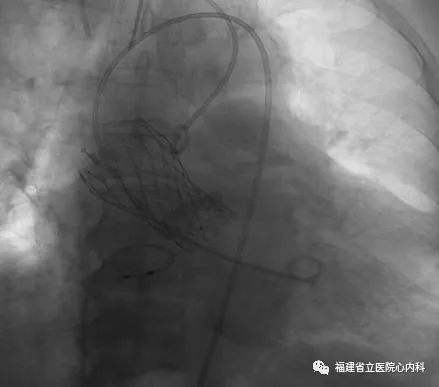

该病例是TYPE0型二叶瓣,瓣叶增厚伴极重度钙化,同时升主动脉增宽且为横位心,导致输送系统通过主动脉弓及瓣膜口难度明显增加,而且瓣上存在限制结构,瓣膜移位风险高,术中手术团队默契配合,输送系统顺利通过主动脉弓及狭窄的瓣口,Venus A-L26瓣膜定位精准释放,达到术前预期锚定位置,最终效果佳。

瓣环

窦部

球囊预扩张

植入L26瓣膜